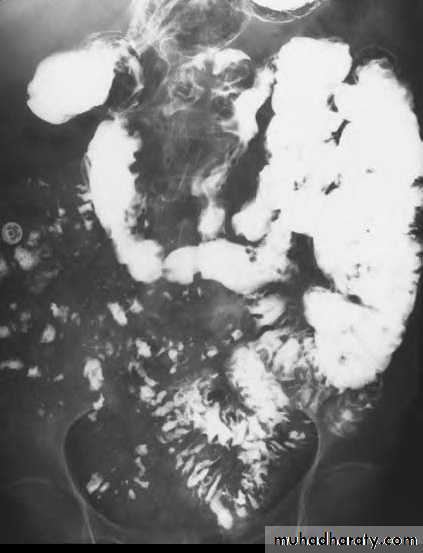

Celiac disease: The jejunum is devoid of most of its normal mucosal markings with Ileal loops in the pelvis have a prominent fold pattern

Celiac disease:

Flocculation and segmentation of barium indicate the presence of excessive fluid in the distal small bowel. The normal jejunal fold pattern also isabsent. These loops appear featureless. A few small bowel loops in the pelvis have thickened folds.